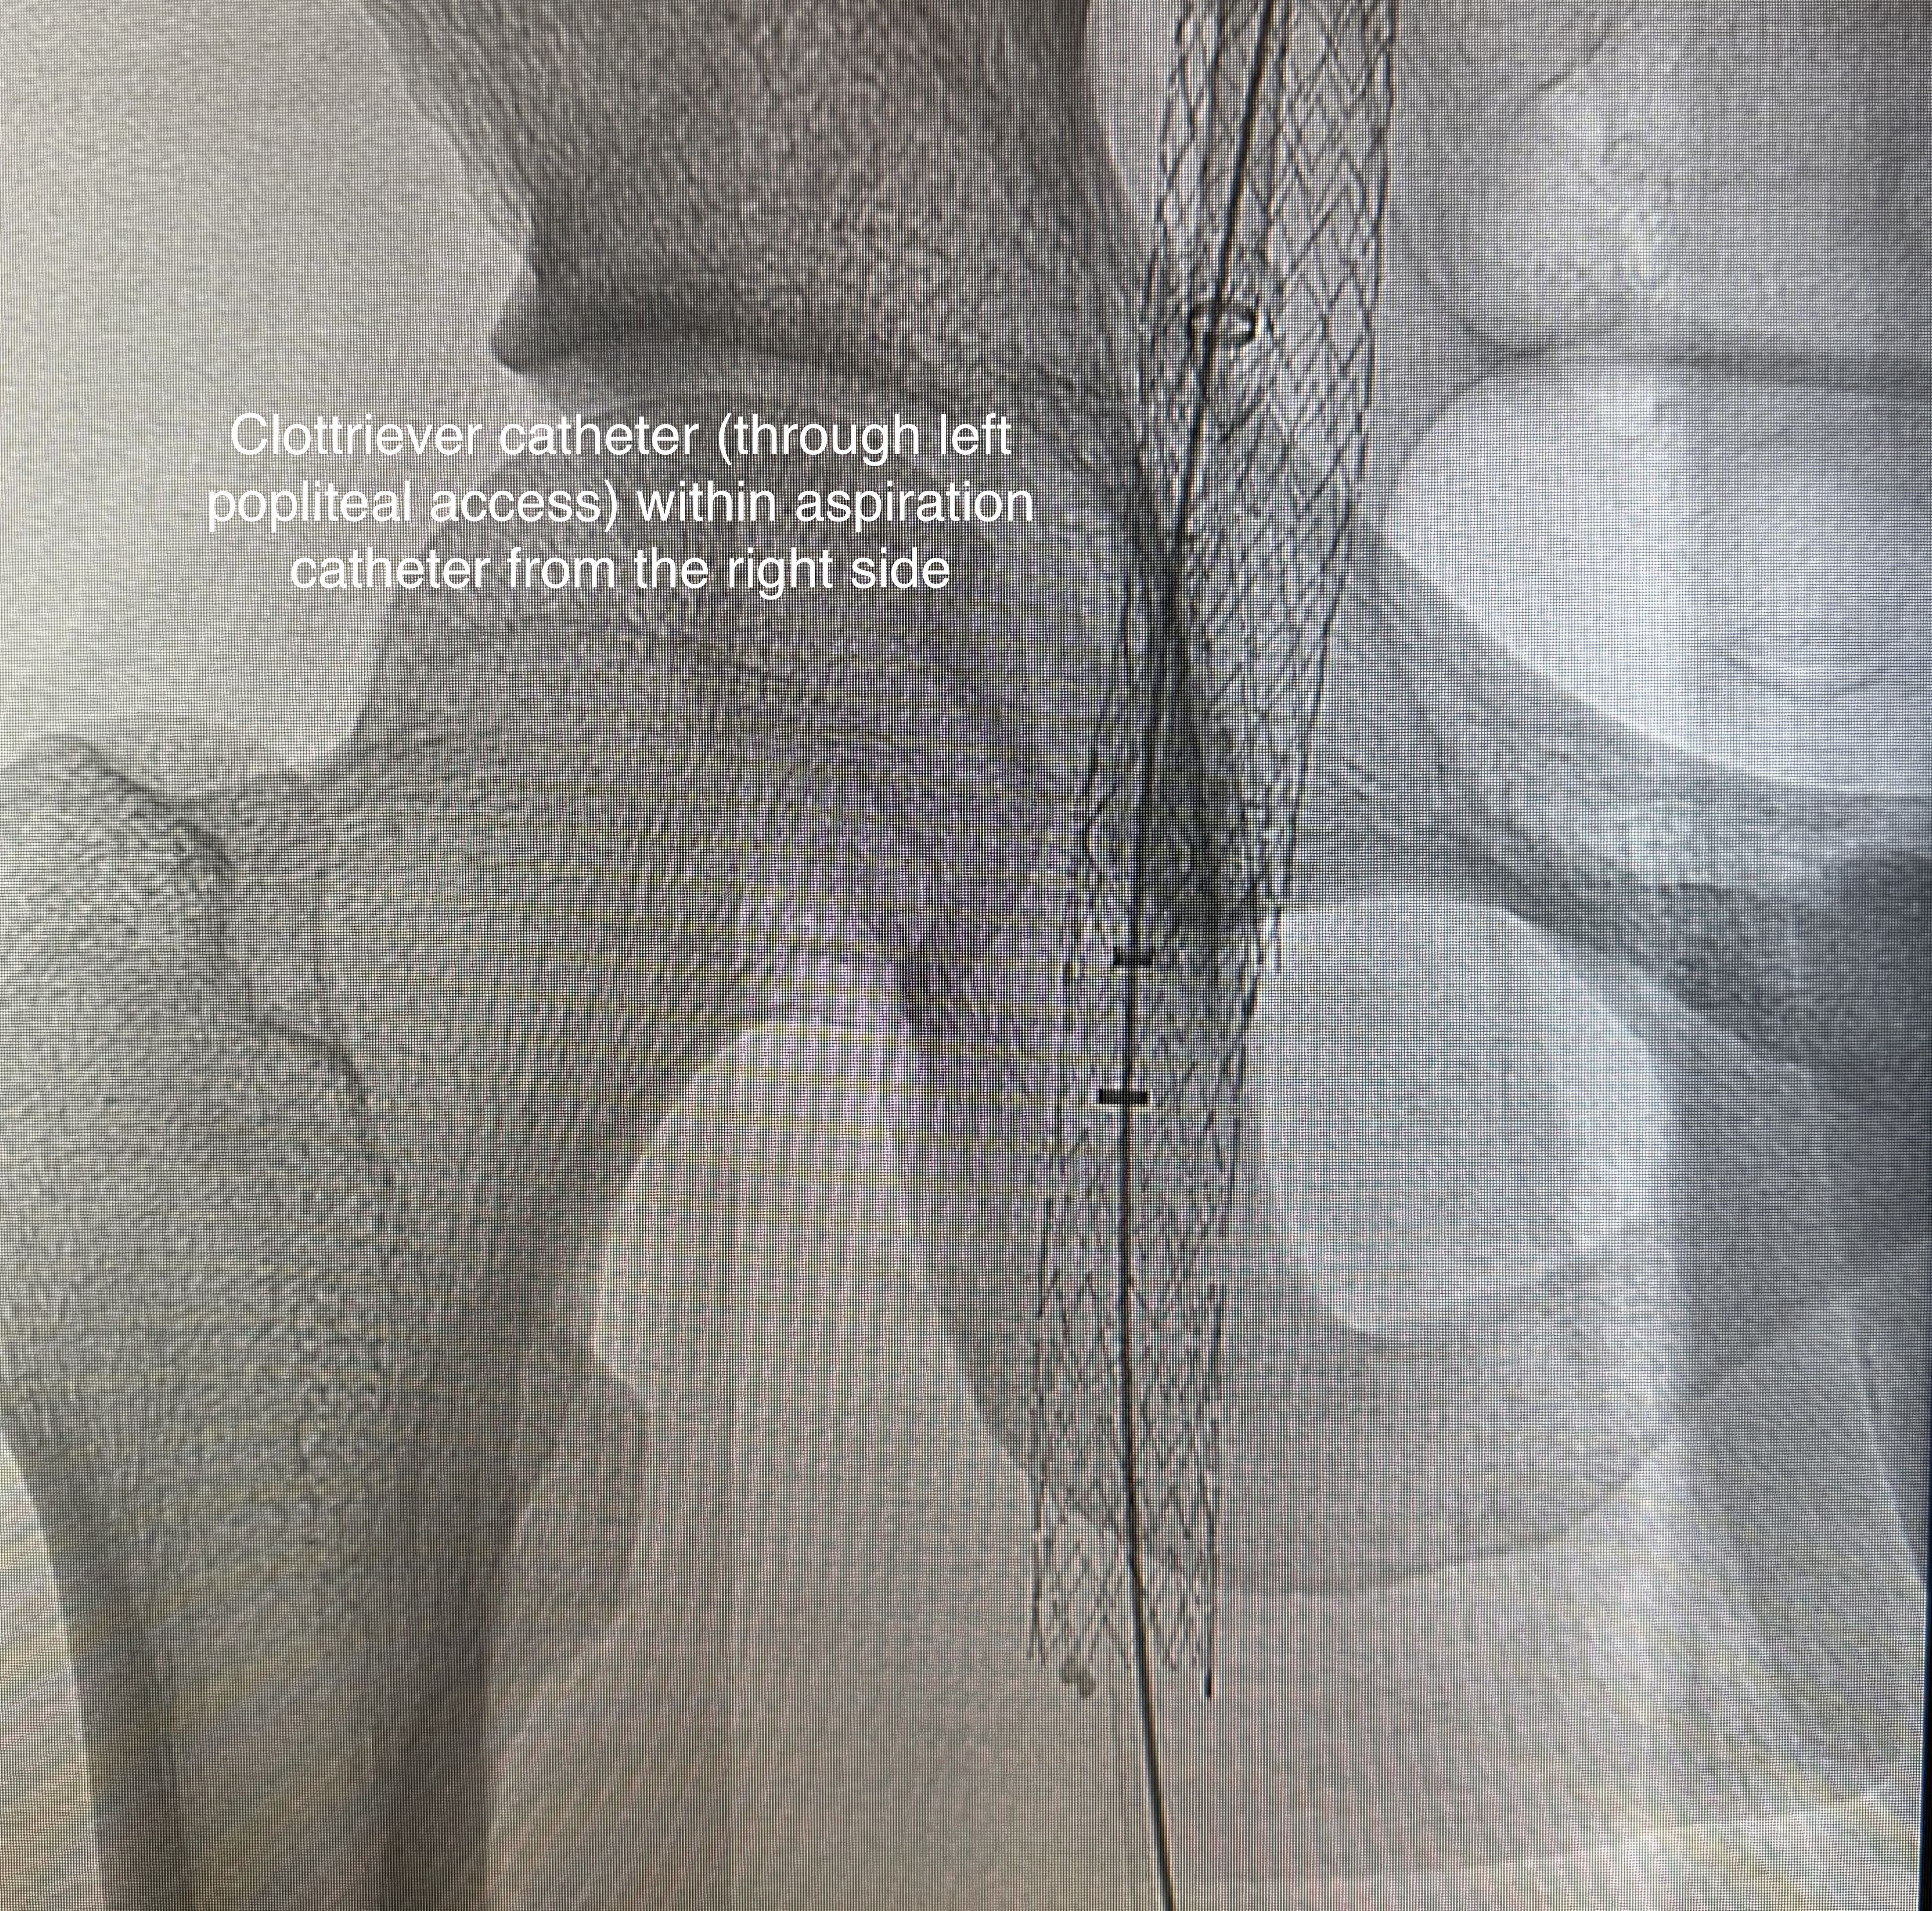

Accesses at right and left popliteal veins were established. A FlowTriever disc was inserted as a temporary inferior vena cava filter via the right popliteal access. Wire was passed through the thrombosed left common iliac to femoral stent. Aspiration thrombectomy was performed and aspirated small amount of chronic blood clots. Subsequent, an "up and over" access was established with a 16 French aspiration catheter inserted through the right popliteal access to the left common iliac stent. The Clottriever catheter was inserted through the left popliteal access into the aspiration catheter. The Clottriever catheter was then retrieved, with simultaneous forward movement of the aspiration catheter to protect the collection basket of the Clottriever catheter from damaging the left common iliac stent during the retrieval process. Moderate amount of blood clots were retrieved with multiple attempts. Balloon angioplasty was then performed and blood flow through the common iliac vein was restored. There was significant improvement in terms of lower limb swelling after the procedure and the patient was discharged later with anticoagulation therapy.